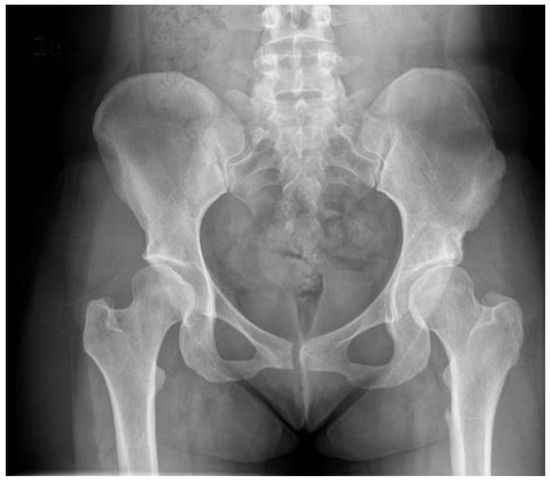

3.2. Radiographic Assessment